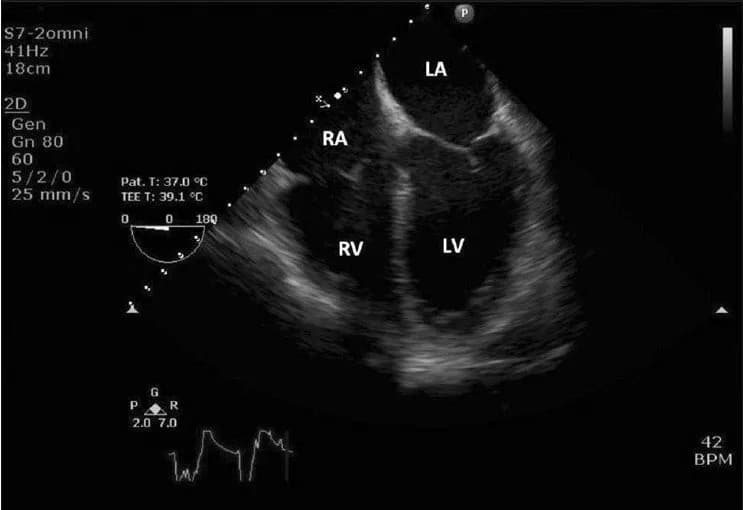

Chỉ định và chống chỉ định siêu âm tim qua đường thực quản

Siêu âm tim qua thực quản: Những điều cần biết

Siêu âm tim qua đường thực quản (TEE) vẫn còn là một khái niệm khá mới mẻ...